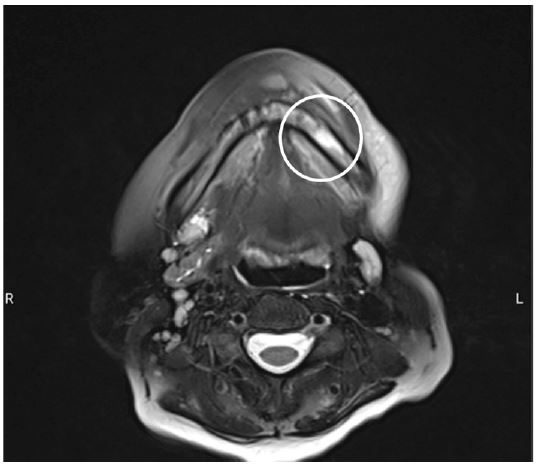

Figure 4: Transversal section on MRI, revealing a left sided decreased signal intensity at the left mandibular corpus on T1-weighted images, consistent with mandibular osteomyelitis.

The left submandibular salivary gland was removed due to the formation of an abscess. Histopathological examination confirmed supportive inflammation with an early granulomatous transformation. Subsequently, an episode of recurrent cervical collection necessitated a week-long admission to the Ear, Nose, Throat (ENT) department, where an Orthopantomograph (OPT) revealed tooth element 37, with no evidence of infection noted. Approximately four weeks post-admission, infliximab administration was interrupted again, due to another recurrence of the cervical abscess that mandated further drainage. Cultures revealed predominant white blood cells with minimal red blood cells. Streptococcus constellatus, sensitive to ampicillin, was once more identified, and the wound continued to produce pus. Two months later, the patient reported pain localized to the left mandibular region. A subsequent CT-scan showed soft tissue air inclusions, without noteworthy osteomyelitic changes or periosteal reactions. Notably, tooth element 37 was absent on this scan, having been previously extracted by the general dentist. Within nine days, the patient sought emergency care due to unbearable pain upon eating and drinking from a recurrent abscess, alongside long-standing numbness along the left mandible, anamnestically revealing incorrect occasional self-administration of amoxicillin/clavulanic acid as a means of pain relief. A Magnetic Resonance Imaging (MRI) scan confirmed left-sided osteomyelitis of the mandible, encouraging the patient’s referral to our department at the university hospital (Figures 3 and 4).